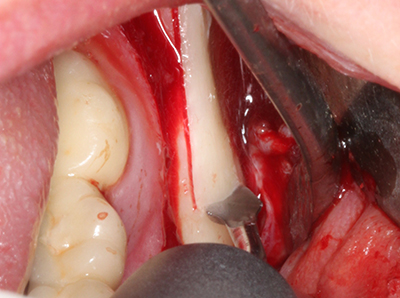

Si es preciso realizar intervenciones quirúrgicas en las que el hueso está en contacto directo con estructuras sensibles, como son los vasos sanguíneos o los nervios, los instrumentos rotativos presentan un enorme potencial de provocar lesiones iatrogénicas. Así, precisamente en la representación de nervios después de una lesión iatrogénica, o en el transcurso de la lateralización de un nervio para resecciones, reconstrucciones o incorporación de implantes, los equipos piezoeléctricos pueden resultar muy útiles para preparar la tapa ósea y retirar las partes de tejido duro cercanas al nervio (fig. 17-20). Por lo general, un ligero contacto del cordón nervioso con el inserto piezoeléctrico no tiene consecuencia alguna; ahora bien, un procedimiento poco cuidadoso con movimientos tipo sierra o piezas de trabajo sobre la base ósea aún existente puede provocar lesiones nerviosas temporales o incluso permanentes. Con todo, el riesgo de sufrir una lesión de este tipo se considera significativamente inferior que en los casos en los que se utilizan sierras y fresas (Pereira, Gealh et al. 2014).

Como ya se ha demostrado en el pasado, básicamente cualquier procedimiento de cirugía de hueso representa una posible indicación para la cirugía piezoeléctrica. Así, la preparación del segmento móvil en la osteogénesis de distracción (fig. 23-25) y en la osteotomía de sándwich puede realizarse con piezas especiales, sin poner en peligro el suministro sanguíneo de la parte crestal, que resulta esencial para el éxito de ambas técnicas (González-García, Diniz-Freitas et al. 2008).